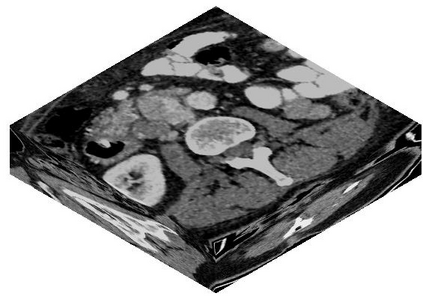

Due to the constraints of the imaging device and high cost in operation time, computer tomography (CT) scans are usually acquired with low intra-slice resolution. Improving the intra-slice resolution is beneficial to the disease diagnosis for both human experts and computer-aided systems. To this end, this paper builds a novel medical slice synthesis to increase the between-slice resolution. Considering that the ground-truth intermediate medical slices are always absent in clinical practice, we introduce the incremental cross-view mutual distillation strategy to accomplish this task in the self-supervised learning manner. Specifically, we model this problem from three different views: slice-wise interpolation from axial view and pixel-wise interpolation from coronal and sagittal views. Under this circumstance, the models learned from different views can distill valuable knowledge to guide the learning processes of each other. We can repeat this process to make the models synthesize intermediate slice data with increasing inter-slice resolution. To demonstrate the effectiveness of the proposed approach, we conduct comprehensive experiments on a large-scale CT dataset. Quantitative and qualitative comparison results show that our method outperforms state-of-the-art algorithms by clear margins.